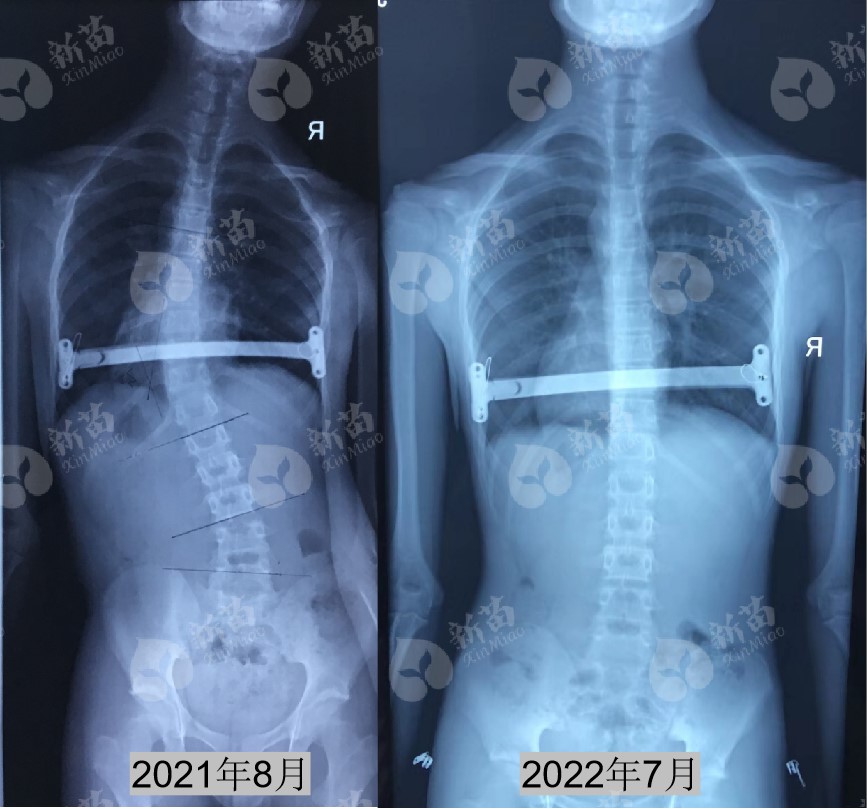

2021年8月,妈妈发现桐桐(化名)出现明显的背部弯曲、高低肩、肩胛骨突出等异常体态。全脊柱X光片显示: 脊柱左侧弯30°,身体躯干偏向左侧,诊断为脊柱侧弯 。

通过11个月的治疗,桐桐的努力有了回报,脊柱侧弯从30°成功矫直!背部外观的高低肩、头偏、躯干偏移、左右腰凹、剃刀背均明显改善!

桐桐在12岁发现脊柱侧弯 Cobb角30° , Risser征3级 , 处于生长发育高峰期 ,存在明显的体态问题,且做过漏斗胸矫正手术,病情较为复杂。但通过新苗综合保守治疗体系治疗,长期密切跟踪随访调整管理,经过近1年的治疗,获得非常显著的矫正效果。

复诊时,桐桐的脊柱侧弯已获得好转,脊柱基本回归到中线上,背部高低肩、头偏、躯干偏移、左右腰凹、剃刀背等体态问题已明显改善。